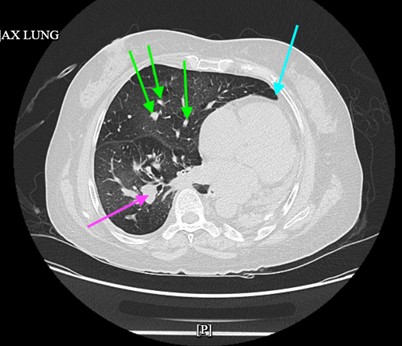

Chest radiography revealed diffuse bilateral interstitial prominence, left basilar consolidation, and a large left pleural effusion (Fig. 1). A non-contrast CT of the chest demonstrated severe emphysema with marked hyperexpansion of the right lung, near-complete destruction and volume loss of the left lung with mediastinal shift, and multiple calcified granulomas (Fig. 2). A 1.2-cm spiculated right lower-lobe pulmonary nodule was identified. CT of the head showed no acute abnormalities. Laboratory testing revealed no leukocytosis, but troponin levels were elevated (83.7→69 ng/L), consistent with type 2 myocardial injury. Serum bicarbonate was elevated (33–39 mEq/L), reflecting chronic CO₂ retention. Her hemoglobin decreased from 12.1 to 10.0 g/dL during hospitalization, and creatinine rose slightly from 0.94 to 1.12 mg/dL. Infectious studies, including a respiratory viral panel, were negative.

Figure 2: Non-contrast CT chest.

Arrows:

● Green = multiple calcified nodules

● Blue = volume loss of the left lung with mediastinal shift

● Pink = 1.2-cm speculated right lower-lobe pulmonary nodule